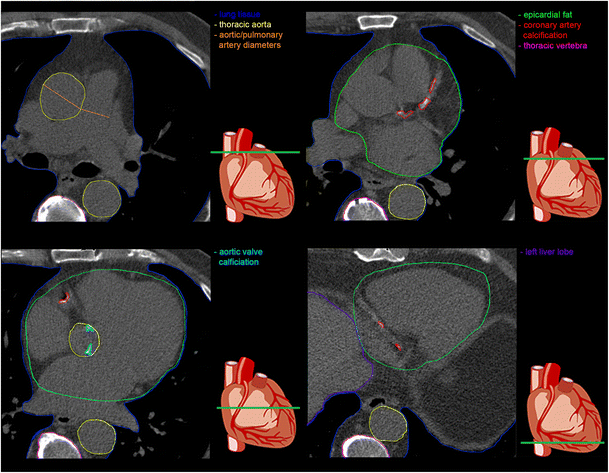

")\].Fig. 1

Imaging markers on non-contrast coronary calcium scans. Four slices of a coronary calcium scan of a single patient showing the heart at different levels with, in colour, the different tissues from which the potential imaging markers may be obtained